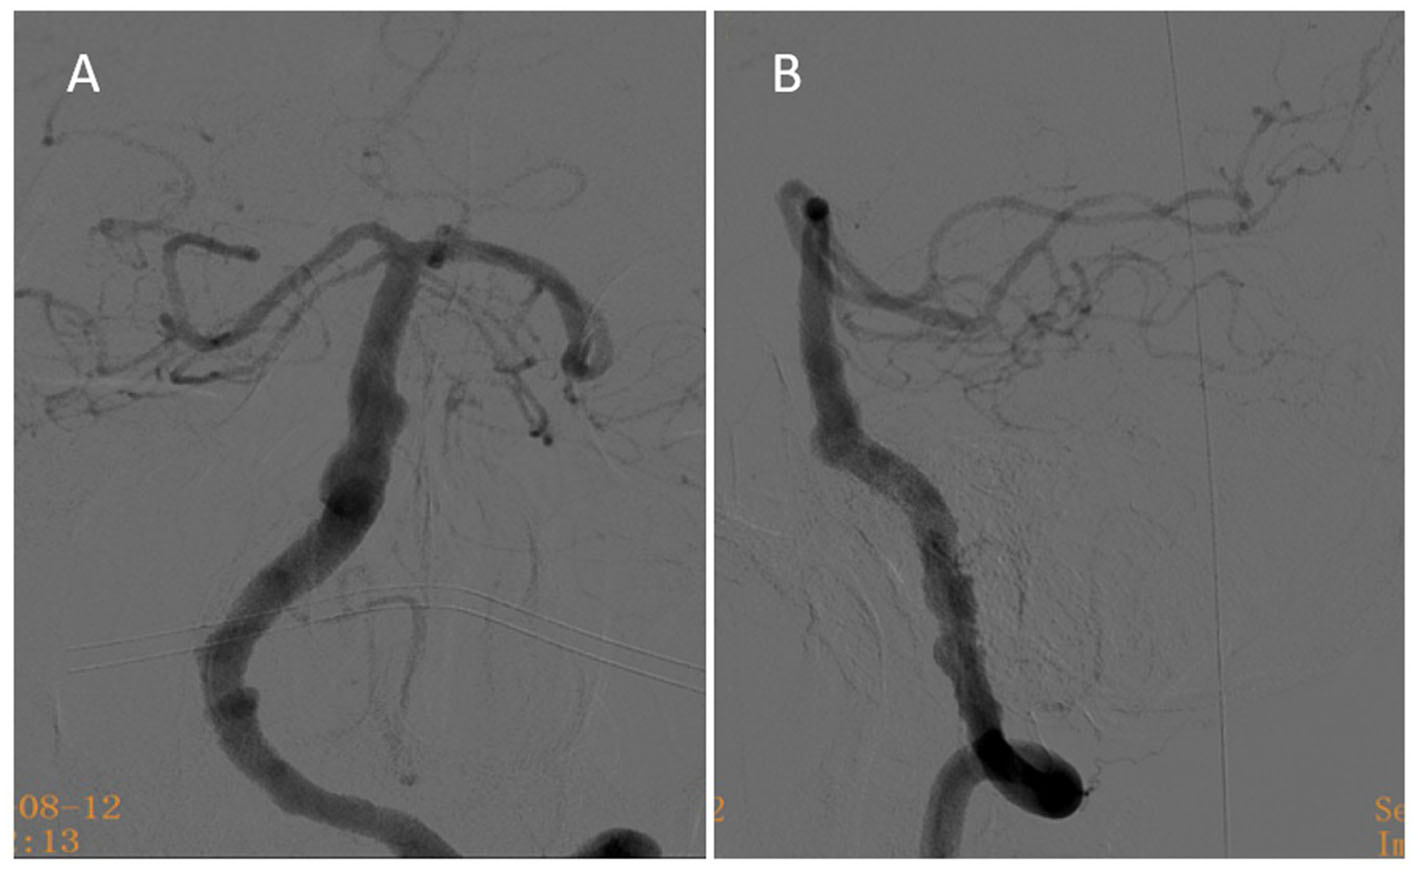

There were no signs of cerebral infarction after the operation, and the patient recovered well. He had no new symptoms after discharge and continued to receive dual antiplatelet aggregation therapy for 6 months. Six months after the operation, the follow-up digital subtraction angiography showed that the aneurysm was almost completely occluded, with OKM grade C (Figure 4). The antiplatelet strategy was then changed to aspirin (100 mg, 1×/d) with clinical follow-up.

Figure 4

Six-month follow-up angiography. (A) At the 6-month follow-up, anteroposterior angiography showed that the aneurysm was nearly completely occluded. (B) At the 6-month follow-up, lateral angiography reveals the aneurysm was nearly completely occluded.